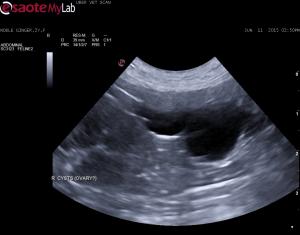

– there are bilateral ovarian cysts (I am assuming this due to their location caudal and lateral to both kidneys)